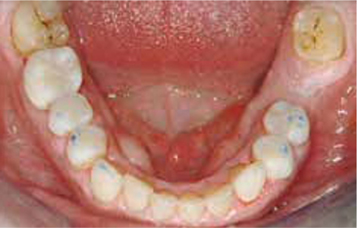

Occlusaal aanzicht van de onderkaak.

Afbeelding vergroten

Bij het extraoraal onderzoek zie ik een lichte hypertrofie van de m. masseter. Intraoraal tref ik een ernstig versleten dentitie aan waarbij de slijtage niet passend bij de leeftijd kan worden genoemd (afbeelding 2-7 en tabel 1) .